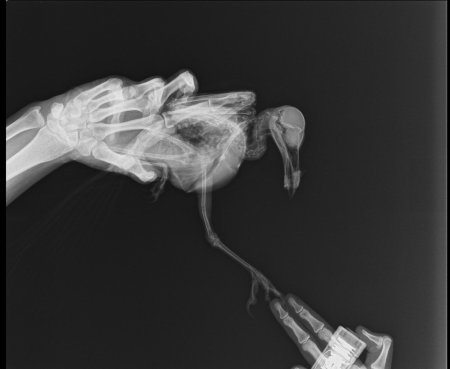

Рентгеновский эффект создает фантастические композиции в этих фотографиях девушки, чье тело становится прозрачным, демонстрируя скелет и внутренние органы. Она позирует в разных позах, ее силуэт светится загадочным свечением. Каждый кадр передает атмосферу научной фантастики и медицинского искусства. Ее кожа кажется полупрозрачной, позволяя увидеть кости и мышцы. Фотографии рассказывают о хрупкости человеческого тела и его внутренней красоте. Девушка то стоит в задумчивости, то делает грациозное движение. Эти иллюстрации вдохновляют на размышления о человеческой анатомии и уязвимости. Каждая картинка - это момент прозрения, когда внешнее уступает место внутреннему. Девушка воплощает образ современной Медузы, сочетающей красоту и загадочность.